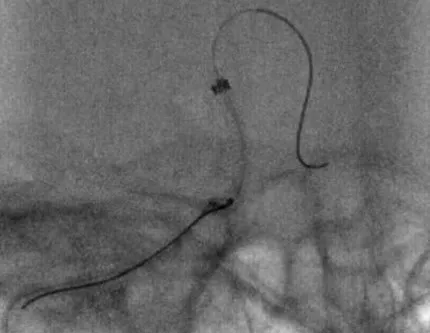

8F指引导管联合6F Navien中间导管,冒烟证实,右侧CCA中段以远未见显影(A),造影证实,右侧ICA窦部以远未见显影(B)

8F指引导管联合6F Navien中间导管,尝试右侧ICA C-C1中部抽吸血栓,结果,抽吸出褐色血栓

8F指引导管联合6F Navien中间导管,通过中间导管造影,提示ICA眼动脉段以远未见显影